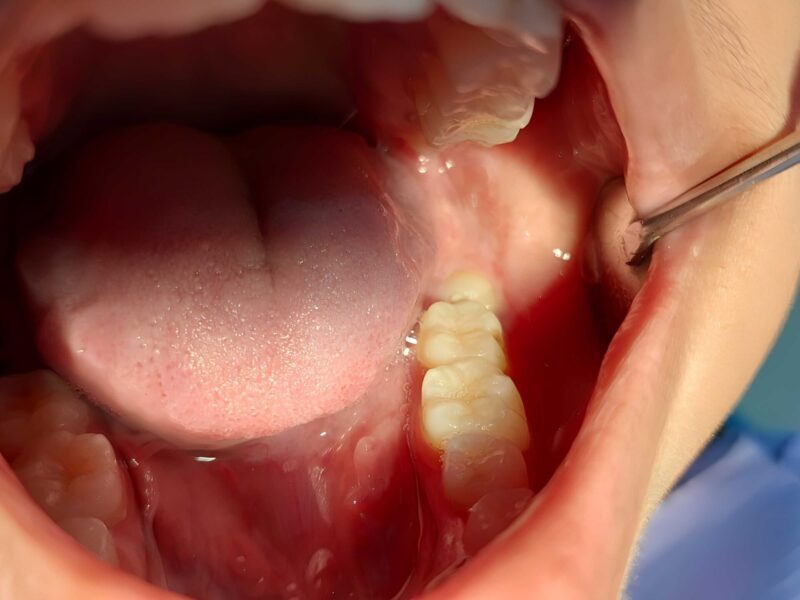

症例紹介

親知らずの抜歯や顎関節症の治療では、患者様の不安や症状にしっかり寄り添いながら、安心・安全な治療を提供しています。

「難しいと言われた親知らず」「顎の不調が治らない」などのお悩みは、ぜひ一度、当院へご相談ください。